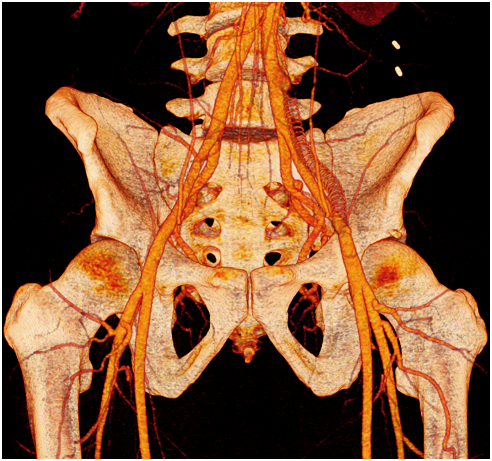

In April 2015, the patient was admitted again in our department due to the appearance in the last 24h of a short distance right lower limb claudication. In this case, the right limb presented a positive femoral pulse, but right popliteal and distal pulses were absent. Left lower limb evaluation was completely normal. The patient confirmed he kept on training and participating in elite triathlon competitions despite our recommendations. Angio CT scan confirmed a new thrombosis, now at the right EIA. Thrombus images and clinical acute presentation indicated there was a fresh, non-fibrotic thrombus in the occluded artery. A hybrid approach was selected. Through a surgical open femoral access, distal femoral control to prevent distal embolism and proximal thrombectomy with Fogarty catheters were performed. In control angiography a short stenosis was observed in the right EIA, requiring a pharmacologic balloon angioplasty with angiographic optimal final result (Figure 3A) (Figure 3B). He was discharged again 24h after the procedure with a normal physical evaluation and double antiaggregant were prescribed. In order to optimize medical treatment, hematologic evaluation was performed in order to evaluate any possible thrombophilic disease. All results were negative. Even though the patient had been informed that intensive sports were the aetiology of the iliac endofibrosis and the ischemic events, he did not stop training and competing. All clinical controls were normal until May 2016, when a new middle distance claudication appeared affecting the right lower limb. Image tests confirmed acute thrombosis of the right EIA, and an endoluminal thrombus aspiration and pharmacologic angioplasty of the right EIA were performed. Functional test and images confirm the resolution of the process (Figure 4). Since this procedure, patient seemed to understand and stopped intensive sport practise and remained asymptomatic in ambulatory controls. Chronic double antiaggregation was recommended. But, the athlete, searching for a diagnosis or therapeutic guidelines that better fit his sporting desires, requested an assessment from the Medical Services at the Olympic Training Center (OTC). In June 2016, in the OTC, during a cycle ergometer exercise test simulating a training session, the ischemic symptoms, right thigh pain, lack of pulse and pale foot, reappeared at the 15 minute at steady state power of 225 watts and 165 beats/min. The circulation recovered very slowly and the pulse did not appear until the 5 minutes of rest. That exercise response demonstrated to the athlete, finally, that an acute ischemic process in response to exercise exists, even while subject maintained drug therapy, previous good vascular diameter and by peripheral doppler scan ultrasound, without changes after short and maximal isometric contraction.

Iliac artery endofibrosis is a challenging pathology because it affects very young people with possible devastating effects but aetiology and therapeutic options remain uncertain. Even though literature raises the idea that open surgical repair is the most definitive option, we consider treatment indication should be individualised in all patients. In this case there are three factors that made our department decide to apply endovascular procedures. The first reason was the existence of a failed prior open surgery. When revising the angioCT scan and angiography images, we identified an important psoas and lumbar muscular hypertrophy that seemed to be the external mechanical reason of the bypass graft obliteration due to an external compression. Furthermore, in angiographic images no significant psoas artery collaterals were observed, thus suggesting that there was no EIA tethering to be solved, and iliac artery elongation was not notorious. It therefore seemed that there were no significant anatomical factors that would benefit from open surgical correction. Instead, in such a young and active patient open surgery carried higher complication rates and longer recovery periods after surgery. Endovascular options are technically feasible, with low and minor complication rates when compared to open iliac revascularizations, and even though these seem to have a limited patency in time, this case shows that endovascular iliac revascularizations are easily reproducible with optimal immediate results and minimal hospital admittance. Nevertheless, either endovascular or surgical procedures fail if the mechanic origin of the iliac artery endofibrosis persists. Our patient underwent intensive clinical controls and a correct medical treatment to enhance endovascular revascularization patency and to prevent thrombotic events, but there was no sport cessation. According to clinical history, acute symptoms usually appeared after competitions of intensive trainings. It seems that this patient had bilateral EIA endofibrosis due to triathlon competitions and training (including intensive cycling sessions), probably due to the external continuous mechanic trauma of hypertrophic lumbar muscles adjacent to the IAE (Figure 5). In this context, some especially intensive efforts involving important dehydration may have led to complication of the endofibrotic area causing the EIA spasm and thrombosis.